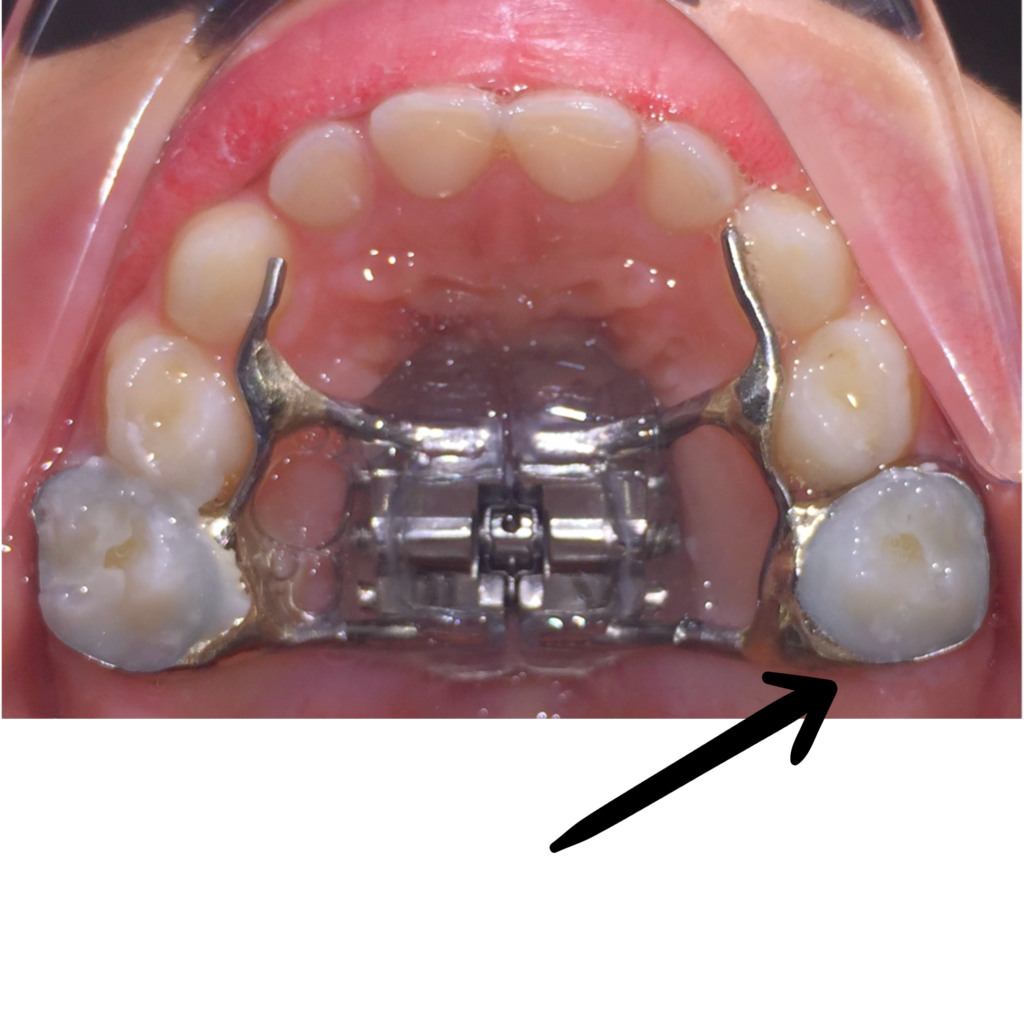

Aparell caigut completament

Aparell desenganxat

Aparell correcte

Aparell trencat